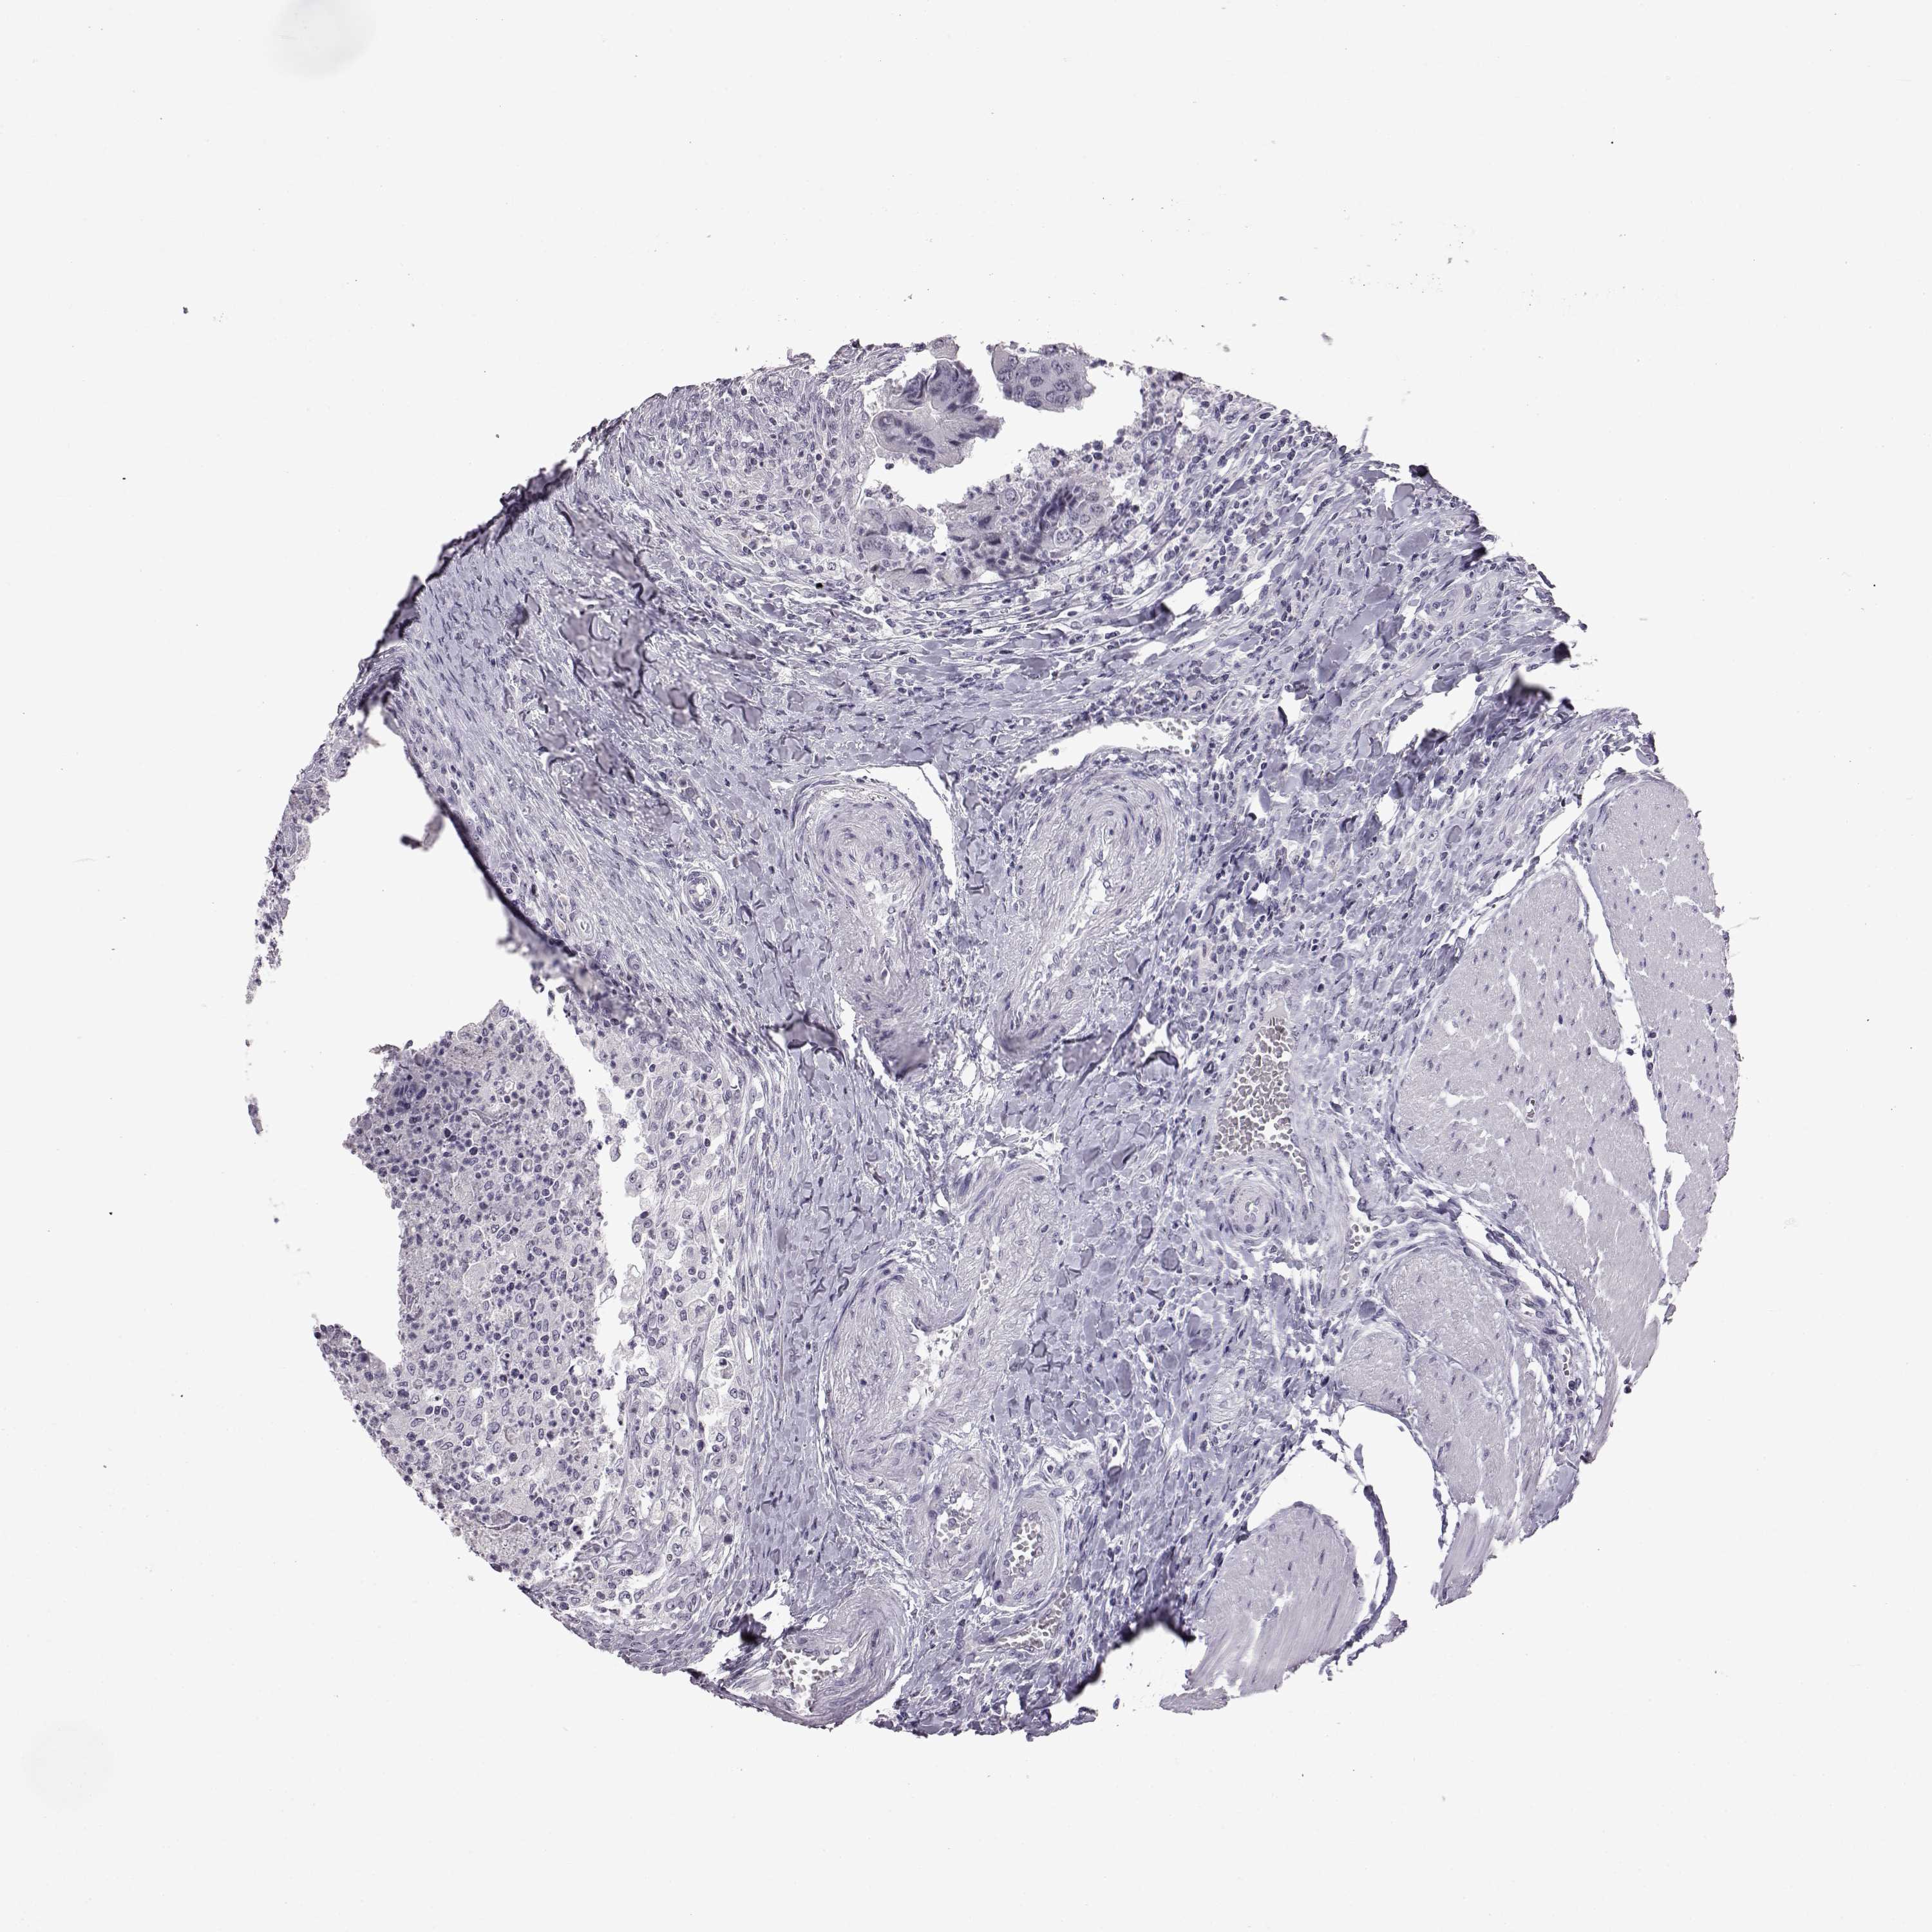

CANCER COLORECTAL CANCER Show tissue menu

Colorectal cancer

Rectum adenocarcinoma